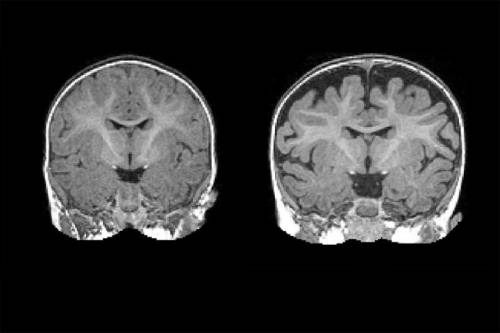

A la derecha se muestra la imagen por resonancia magnética de parte de la cabeza de un bebé que fue diagnosticado con autismo a los 2 años. El espacio oscuro entre los pliegues cerebrales y el cráneo indica cantidades mayores de fluido cerebroespinal. A la izquierda se muestra la imagen por resonancia magnética de un bebé que no fue diagnosticado con autismo a esa edad. Nótese la cantidad inferior de fluido cerebroespinal. (Fotos: Carolina Institute for Developmental Disabilities (UNC-Chapel Hill))

La red de investigación liderada por el Dr. Joseph Piven, de la Universidad de Carolina del Norte en Chapel Hill, Estados Unidos, ha encontrado que muchos bebés diagnosticados con autismo a los dos años de edad tenían una cantidad sustancialmente mayor de fluido cerebroespinal (líquido cefalorraquídeo) extraaxial a los 6 y a los 12 meses de edad, antes de que el diagnóstico fuera posible. También han hallado que cuanto más fluido cerebroespinal extraaxial haya a los seis meses de edad, medido a través de resonancia magnética, más severos serán los síntomas del autismo a los dos años de edad.